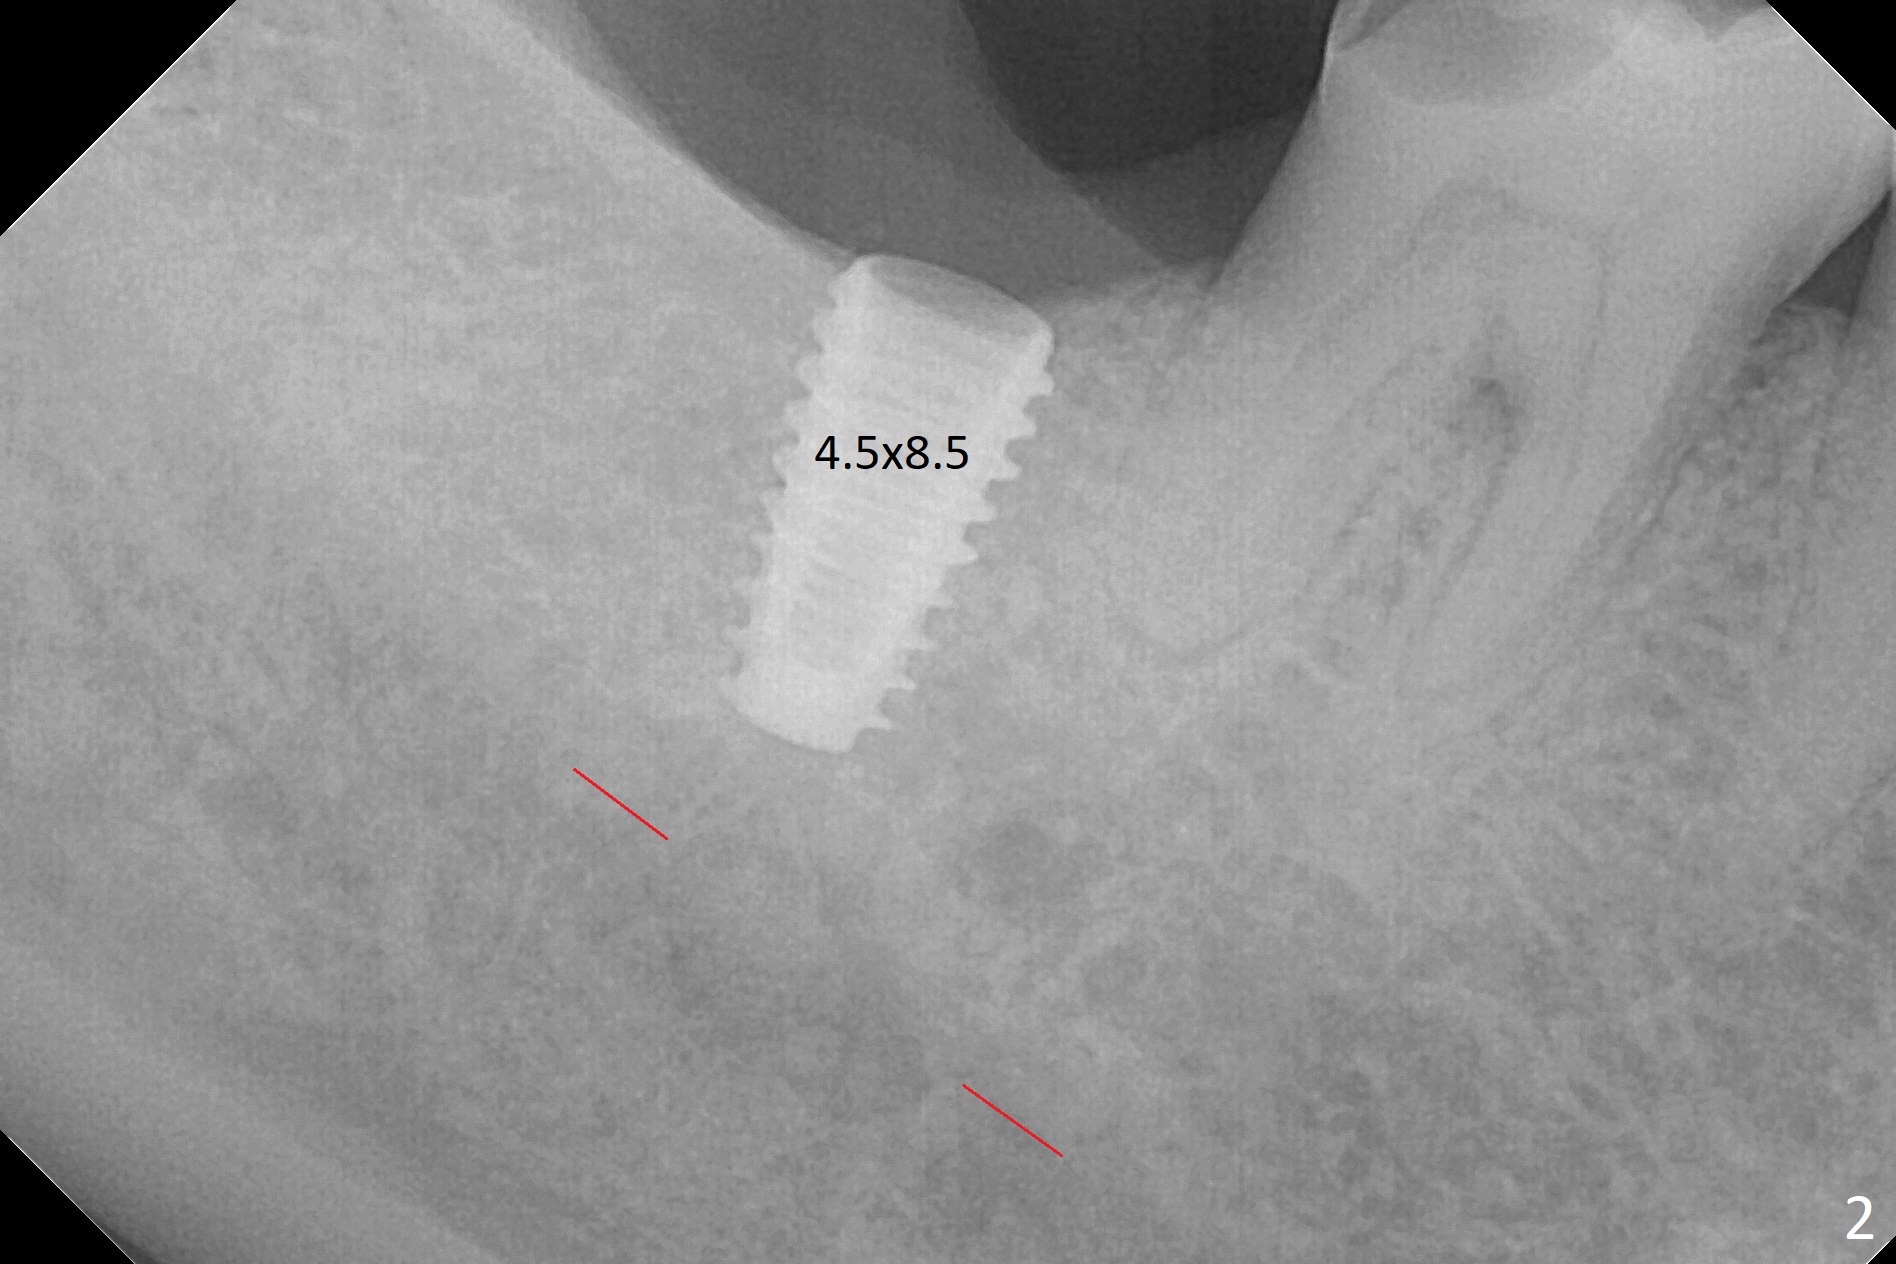

The ridge at #31 is wide buccolingually, but uneven with buccal lower. When a 3 mm drill reaches 13 mm in depth (Fig.1 (gingival level, flapless with Magic Split)), the patient feels pain with the osteotomy close to the Inferior Alveolar Canal (red dashed line). Subsequent osteotomy depth gradually reduces to 11.5 and 10.0 mm before placing a 4.5x8.5 mm implant initially with high torque. After rewinding, the implant is placed deeper (Fig.3 (implant plateau being even with the buccal crest)); a 5.5x4(2) mm healing abutment is placed due to severe supraeruption of the tooth #2. The patient refuses orthodontic intrusion. A prepped 5.5x4(2) mm cemented abutment is placed 6.5 months postop (Fig.3). After reduction of the lingual cusp of the tooth #2 (barely clearance), a provisional is fabricated at #31 to intrude the opposing tooth.